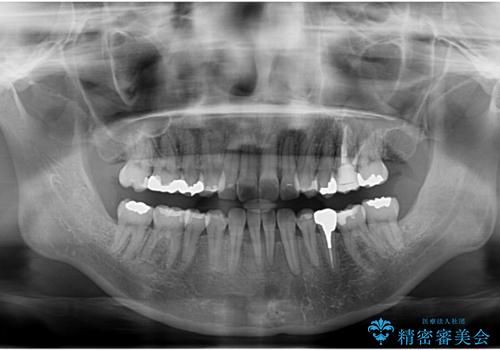

全体的な虫歯治療 銀歯をセラミックに

- 当院で矯正治療後、虫歯治療を一通り行いました。

矯正治療後はリテーナーを使用する必要がありますが、両方同じ病院で行うことにより、リテーナーの再作成や修理もしっかり対応できます。